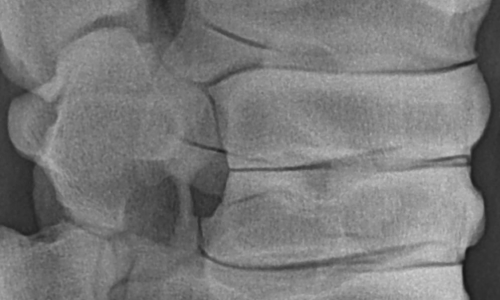

Röntgenaufnahme einer Pferdewirbelsäule